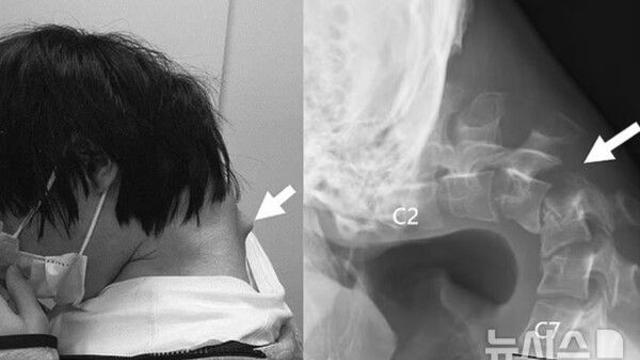

스마트폰 게임 중독 때문?…목 90도로 꺾인 日 남성, 결국 수술까지